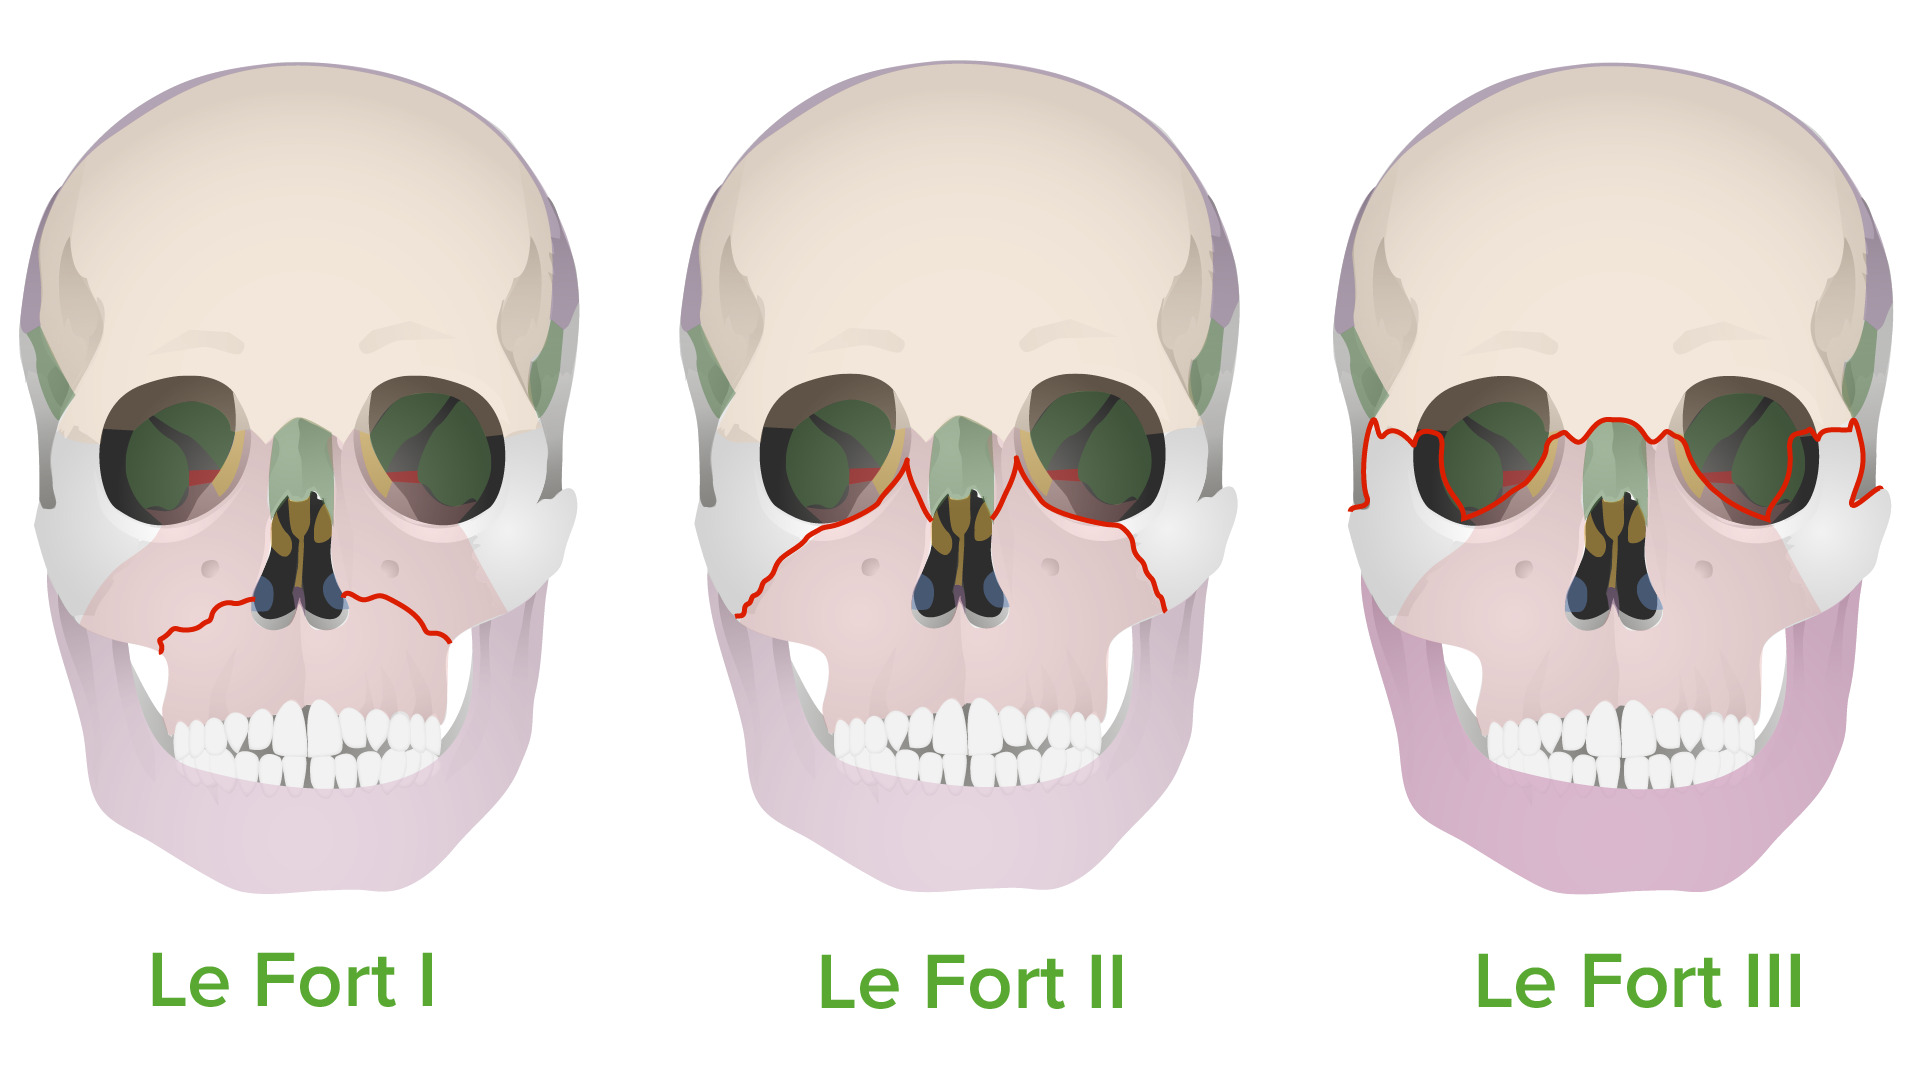

Im like perfect fucking candidate for lefort 1

Im like perfect fucking candidate for lefort 1